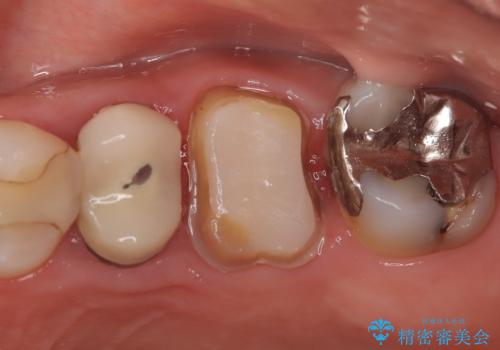

【破折ファイル除去】他院で折れた根管治療の器具をとってほしい

- 他院で折れた根管治療の器具をとってほしいという主訴で来院されました。

マイクロスコープで根管内を観察すると、除去できる状態だったため破折ファイル除去を行いオールセラミッククラウンにて修復治療しております。